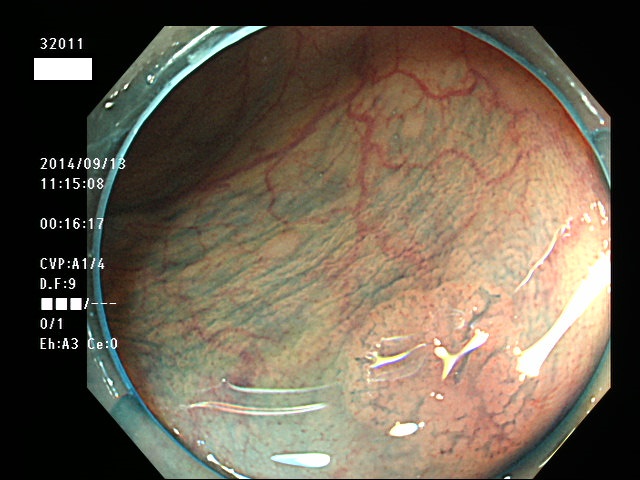

上記100名より抽出した平坦・陥凹型腺腫(=癌化の危険が高いが見落としやすい病変)の内視鏡写真